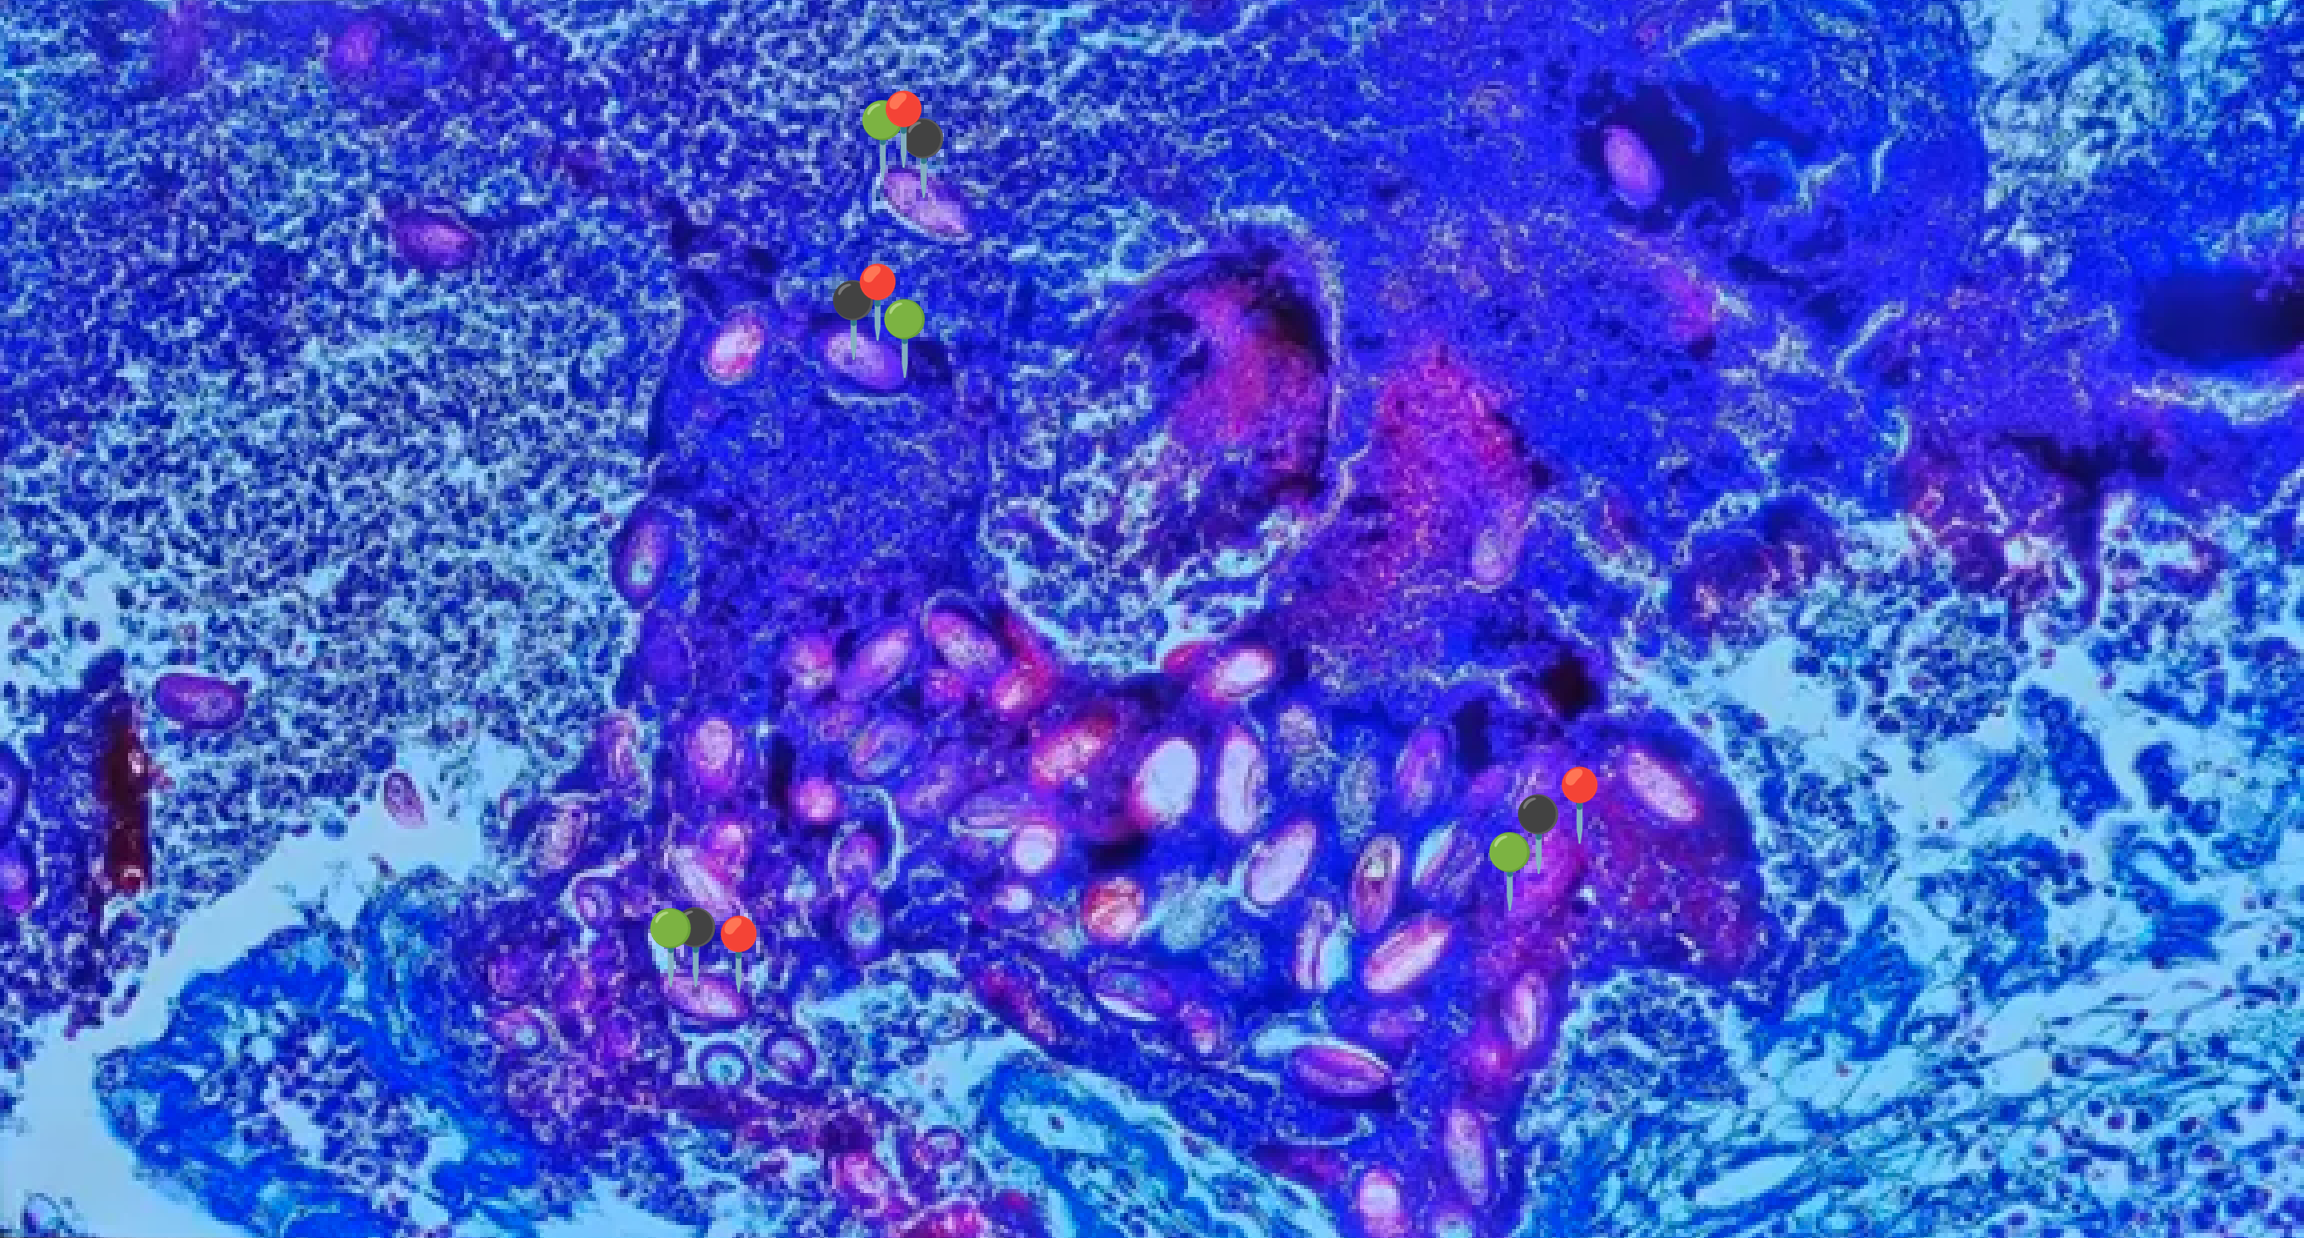

🔷🪳 Leishmania donovani (Amastigota)

😷❓ Parazytoza: Leiszmanioza

🧩🦠 Organelle:

🟣 - jądro komórkowe; wici są zredukowane i niewidoczne.